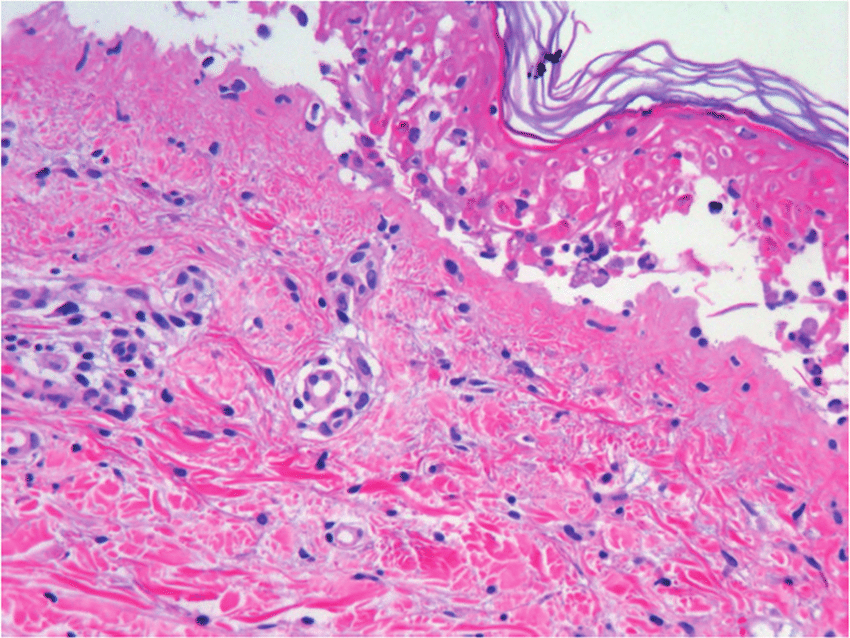

Si bien los criterios de inclusión más estrictos y la eliminación de casos duplicados dieron lugar a menos casos identificados de osteonecrosis de la mandíbula relacionada con medicamentos (ONMRM) en general en comparación con investigaciones anteriores, nuestros datos representan un análisis más confiable de los informes de ONMRM a la base de datos FAERS. Denosumab fue el medicamento más frecuentemente asociado con la ONM. Si bien no podemos implicar las tasas de incidencia de nuestros datos debido a la naturaleza de la base de datos FAERS, nuestros hallazgos brindan una descripción más detallada de los diversos medicamentos asociados con la ONM y aclaran los datos demográficos de los pacientes asociados con la RAM. Además, nuestro estudio identifica casos de varias drogas y clases de drogas recientemente descritas que no se han descrito previamente en la literatura. BMC Pharmacol Toxicol, 6 de marzo de 2023